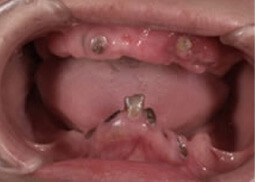

術 前

術前

初診時87歳、男性。上顎は歯周病により残存歯を長期的に機能させることが困難と判断し、全て抜歯。出来る限り早期の咬合機能の回復と審美性の実現が求められ、上顎は「4本のインプラントで失った全ての歯を固定し、手術当日から噛む機能を回復させることが可能」なオールオン4という術式を選択。オールオン4は「治療期間」「経済性」「審美性」「外科的侵襲」などのあらゆる負担を軽減した全く新しいコンセプトの画期的なインプラント治療です。 下顎の欠損部位に対しても、術前の診査診断をしっかり行い合計5本のインプラントを埋入しました。